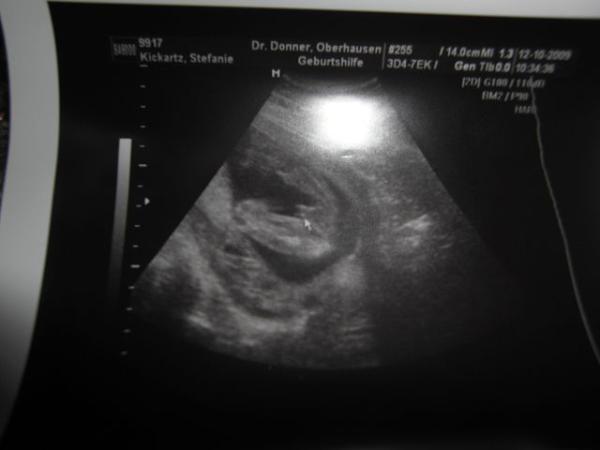

hier mein Junge

Bild zu